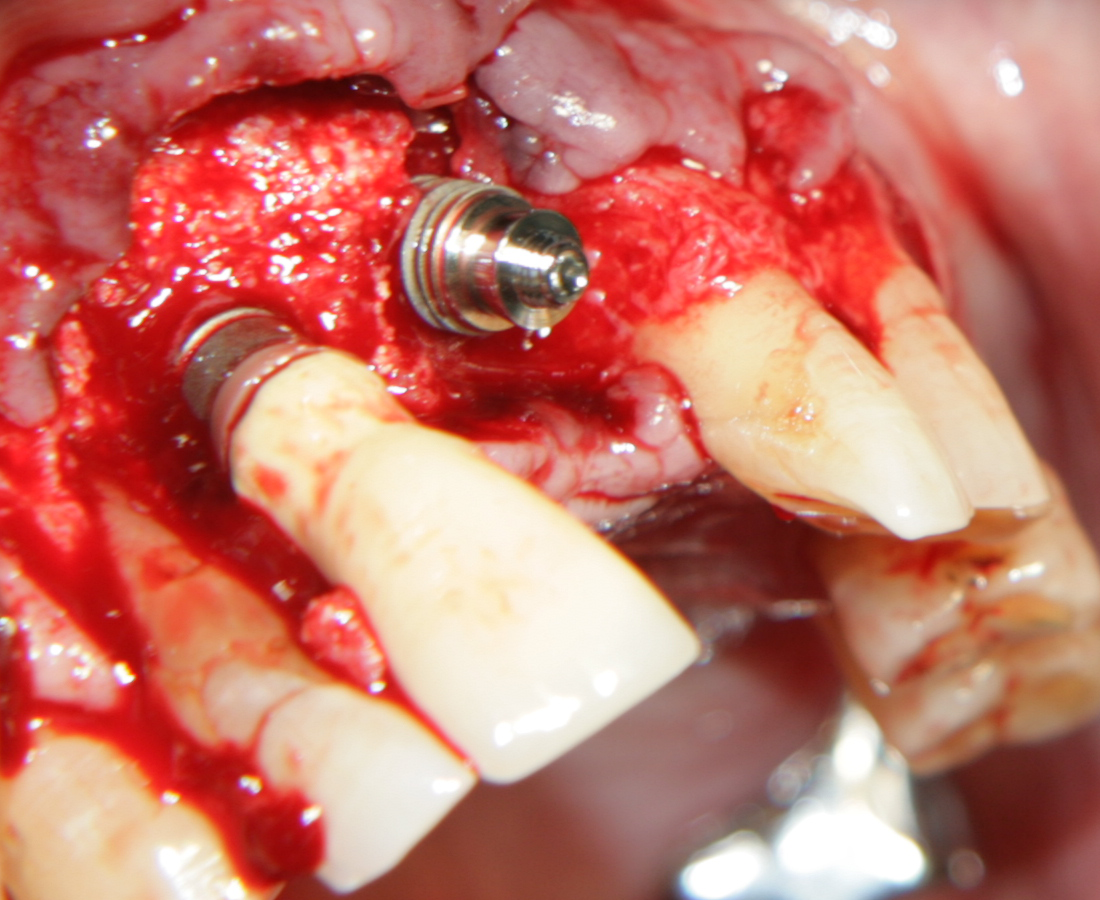

На тази снимка се вижда зъбната алвеола след изваждането на зъба. Формата на алвеолата е изключително подходяща за имедиатно имплантиране - кръгла, без междукоренови прегради, с добре запазени костни стени. Вестибуларно се вижда костен израстък, който бързо би се лизирал ако не се постави имплантат - всяка структура в организма, която не е подложена на функционално натоварване, започва да атрофира много бързо. Поради това всички автори в световната литература са единодушни за един факт: имедиатното имплантиране предпазва от костна загуба поради липсата на време за афункционална атрофия. В този ред на мисли описаният случай на имедиатно имплантиране има много по-добра прогноза, отколкото ако се изчака оздравяването на екстракционната рана.

Имплантатът е поставен в костта. Вижда се покривният винт, който е оцветен в синьо. В периферията се вижда т.нар. bevel design на имплантатите - скосен дизайн, който улеснява работата на имплантолога и най-вече на вносителя на имплантатната система. Улеснението е голямо - скосеният дизайн позволява да се прилагат универсални надстройки за по-тесни и по-широки импланти. Освен това скосяването на имплантата предпазва от костна загуба - възпалителният инфилтрат от операцията мигрира над импланта и медиаторите на възпалените упражняват своето действие там. Някои от тези медиатори могат да причинят тъканна автолиза; очевидно не е възможно да разрушат титана. Повече информация за вътрекостните импланти... При гореописаната клинична ситуация е напълно възможно да се изчака много кратък оздравителен период и да се постави надстройка и корона, т.е. да се извърши имедиатно имплантиране + имедиатно натоварване. Така и постъпихме в случая. Спрямо научните схващания от 80-те и началото на 90-те години това е звучало като ерес и е било достатъчно основание извършителят да бъде разпънат на кръст, изгорен на клада или обесен, а понякога и двете заедно; в днешно време обаче има достатъчно натрупани клинични наблюдения и до голяма степен такъв тип лечение се превръща в стандартна процедура. Вход в нашия форум

Меките тъкани са отпрепарирани и зъбът е екстрахиран. Вижда се

обширен костен дефект - почти няма стени, само обширно

хлътване. На мястото на апекса на зъба се вижда остатък от алвеола